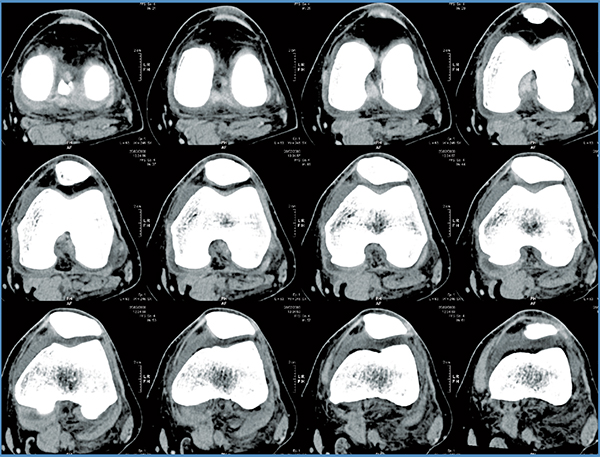

Based on the severity of the arthritis in the knee, total or partial knee replacement may be recommended by a surgeon. Both procedures involve the orthopaedic surgeon guiding the Mako Robotic-Arm to remove diseased bone and cartilage.

- Mako Robotic-Arm Assisted Partial Knee replacement is a treatment option for adults living with early to mid-stage osteoarthritis (OA) that has not yet progressed to all three compartments of the knee. Depending on where the arthritis affects the knee, patients may have an implant inserted in any of the following areas:

- In comparison, Mako Robotic-Arm Assisted Total Knee replacement is a treatment option for adults living with mid to late-stage osteoarthritis of the knee. With Mako Total Knee replacement, the entire knee joint is replaced and the surgeon inserts a Triathlon Total Knee implant. With over a decade of clinical history, Triathlon knee replacements are different than traditional knee replacements because they are designed to work with the body to promote natural-like circular motion.5-8